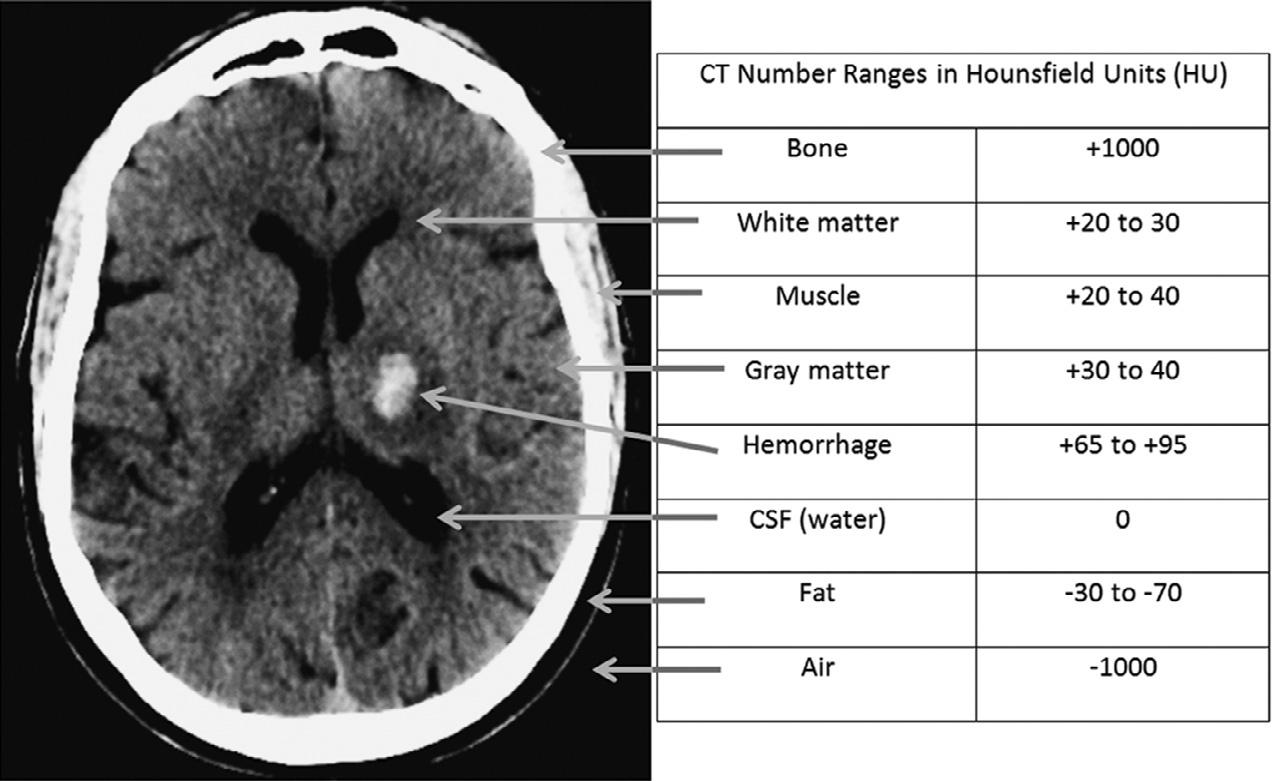

Forexample,atroutineCTX-raybeamenergiesof 120–140kV,theHUvalueofairisapproximately –1000andtheHUvalueofdensecorticalboneisapproximately+1000.Fat,whichfloatsonwater(i.e.,isless dense)istypicallyinthe –30to –70HUrange.Whitematterisabout25HU,graymatterabout35HU,andsoft tissueabout20–30HU.ThestandarddeviationofHU valuesisusuallyinthe 10–20%range.TheHUvalue of invivo bloodis(notsurprisingly)proportionalto thehematocritlevel,andtypicallyabout30.Extravascular,intracranialblood,however,clotsrapidly,andas plasmaisextrudedandresorbedfromtheclot,theconcentrationofthehemoglobinproteincandoubleandtriple,sothatintracranialhemorrhagetypicallymeasures 60–90HU(butrarely >100)(Fig.1.1).Animportant caveatwithregardtoevaluatingtraumapatientsisthat notallpotentialforeignbodiesarehigh-density,highHUstructures.TheCTnumberofadry,woodenforeign body,forexample,istypicallyinthe –100to –170HU range,duetodrywood’sair-filledporousmicrostructure(Yamashitaetal.,2007)(Fig.1.2).

Fig.1.1. Axialcomputedtomography(CT)imagewithsampletypicalCTnumbersinHU.CSF,cerebrospinalfluid.